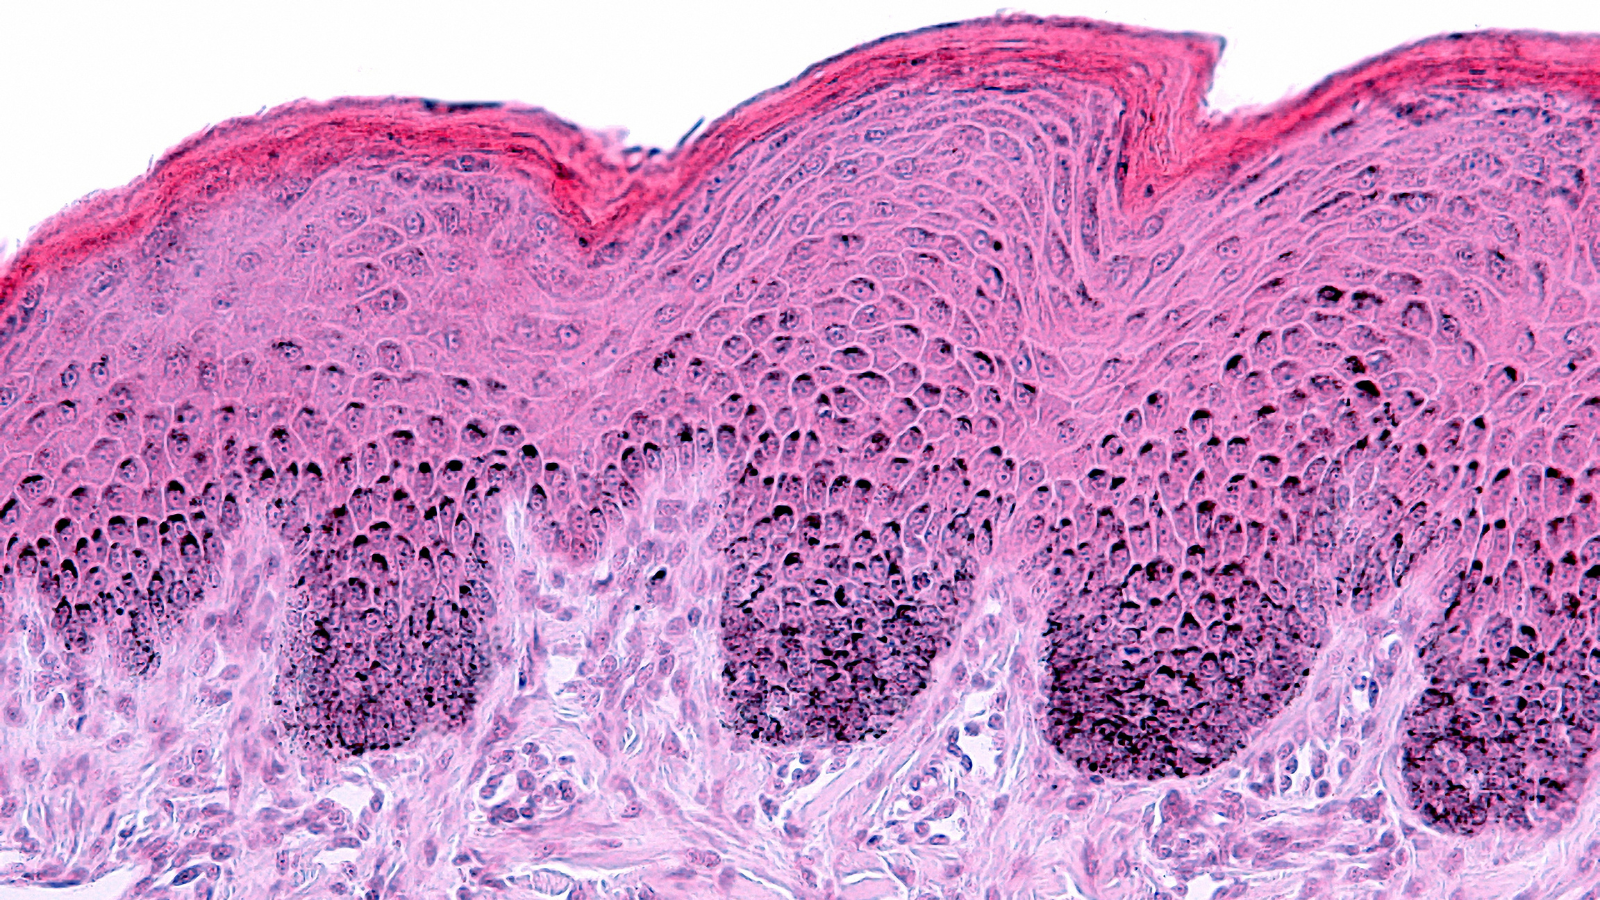

Our new white paper examines the biological drivers of skin aging and details how advanced, non-invasive techniques are transforming clinical evaluation. By combining imaging, biomechanical assessment, biomarker analysis and hydration and barrier function measurements, researchers can now generate multi-dimensional data to scientifically substantiate product claims.

- Key mechanisms of skin aging

- Non-invasive tools for assessing skin longevity